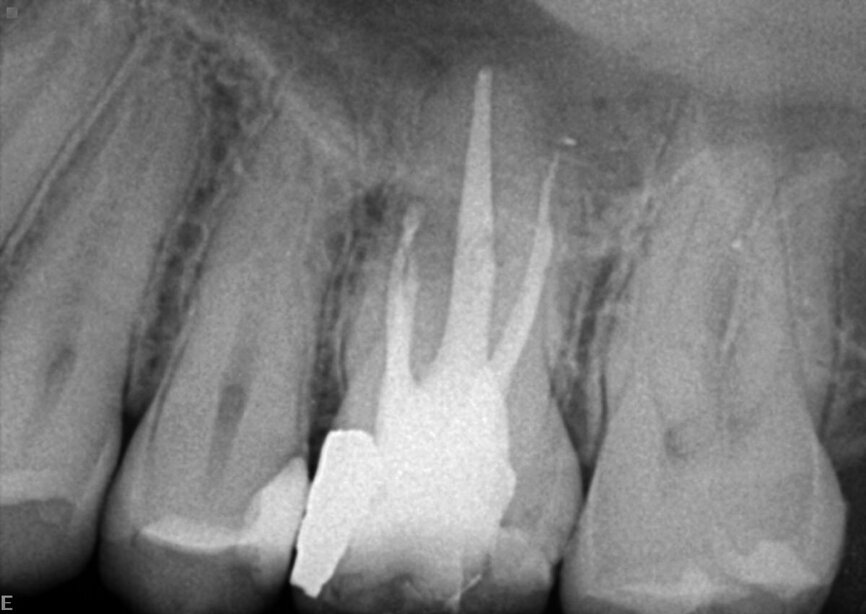

Le patient avait été adressé au cabinetpour une douleur sourde qui affectait une molaire supérieure. Sur la radiographie préopératoire, nous pouvions observer toute une série de matériaux d’obturation, notamment des mono-cônes, des colles composites et des cônes d’argent, dont certains étaient déjà fragmentés. L’un des fragments dépassait de la racine. Après un examen minutieux du sinus et de la membrane, nous avons pu constater que celle-ci avait été perforée en raison du processus inflammatoire et de l’infection qui avait provoqué une sinusite (Fig. 15).

J’ai pratiqué l’intervention sous un microscope opératoire et ai utilisé des inserts ultrasoniques et des limes rotatives K3 XF (Kerr Dental), pour extraire tous les anciens matériaux d’obturation du système canalaire. J’y ai alors inséré un tampon de ouate sec et place un ciment provisoire, car le patient se sentait fatigué après cette longue séance de traitement (Fig. 16). La figure 17 montre quelques débris mineurs des cônes d’argent qui avaient migré au-delà de l’apex radiculaire mésiale. J’ai pu extraire un petit morceau du cône d’argent au moyen de la macro canule du système Endovac et effectuer un nettoyage chimique du système canalaire.

La figure 18 montre la situation immédiatement après l’intervention, en particulier l’obturation des canaux mésiaux. Il est possible d’observer une légère amélioration de la membrane de Schneider et du sinus. La figure 19 a été prise au cours de la visite de suivi a trois mois et montre une fermeture presque complète de la membrane et de l’os du plancher sinusien.